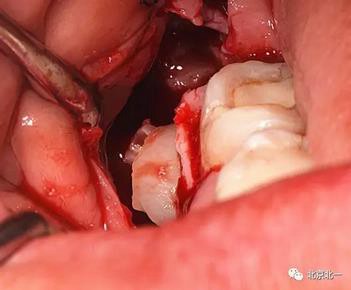

圖六:切開翻瓣, 看見骨面清晰,未見智齒

圖七:去骨后看不見牙齒位置方向。顏色無法區(qū)分,拍片確認一下剛才去骨的以及截的冠就是智齒。

圖八:把牙根優(yōu)先取出后還是看不見牙冠在哪里,實在貼的神經(jīng)管太近, 只能再次拍一個cbct確認。

圖十:實際情況:看到么在第二磨牙頰側接近近中區(qū)域。關鍵牙顏色和骨顏色一致, 只有牙冠部分是白色能看出來, 但是它卻深深的把頭埋下。